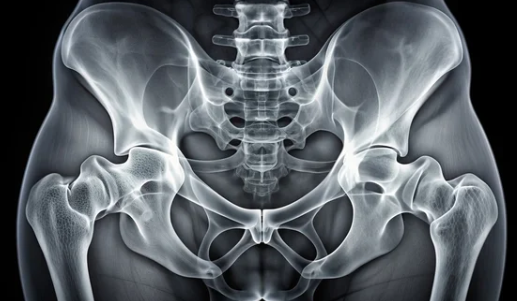

골반 틀어짐, 몸의 불균형 신호! 방치하면 만성 통증까지, 6가지 증상으로 알아보는 골반 건강 체크

혹시 다리 길이가 달라 보이거나, 한쪽 신발 굽만 유독 빨리 닳는 경험을 해보셨나요? 잦은 허리 통증이나 골반 통증으로 고생하고 있지는 않으신가요? 이러한 증상들은 '골반 틀어짐'의 신호일 수 있습니다. 골반은 우리 몸의 중심을 잡아주는 중요한 역할을 하지만, 잘못된 자세나 생활 습관, 외상 등으로 인해 쉽게 틀어질 수 있습니다. 골반 틀어짐은 단순히 불편함을 넘어 체형 불균형, 만성 통증, 소화 장애, 생리 불순 등 다양한 문제를 일으킬 수 있습니다. 오늘은 골반 틀어짐의 증상과 원인, 그리고 교정 및 예방 방법까지 자세히 알아보고 건강한 몸을 유지하는 방법을 함께 살펴보겠습니다.